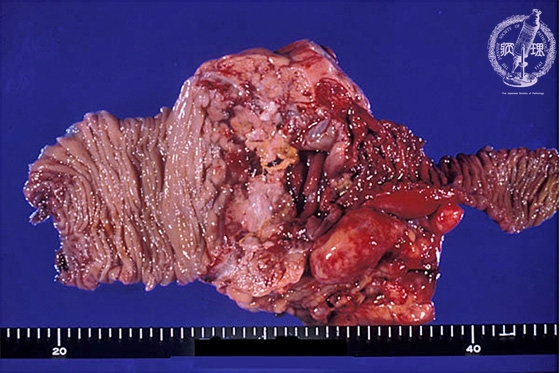

- 9.Small intestine, Large intestine

- (6)Amoebic dysentery

Gross appearance (surgical specimen): Ulcer formation is observed in the ileocecum (image, center).